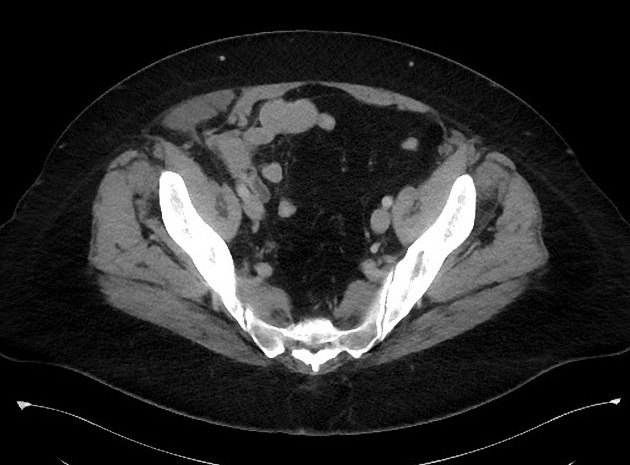

Thoát vị thành bụng

» Thông tin: Nữ giới – 50 tuổi.

» Lâm sàng: Đau hố chậu phải.